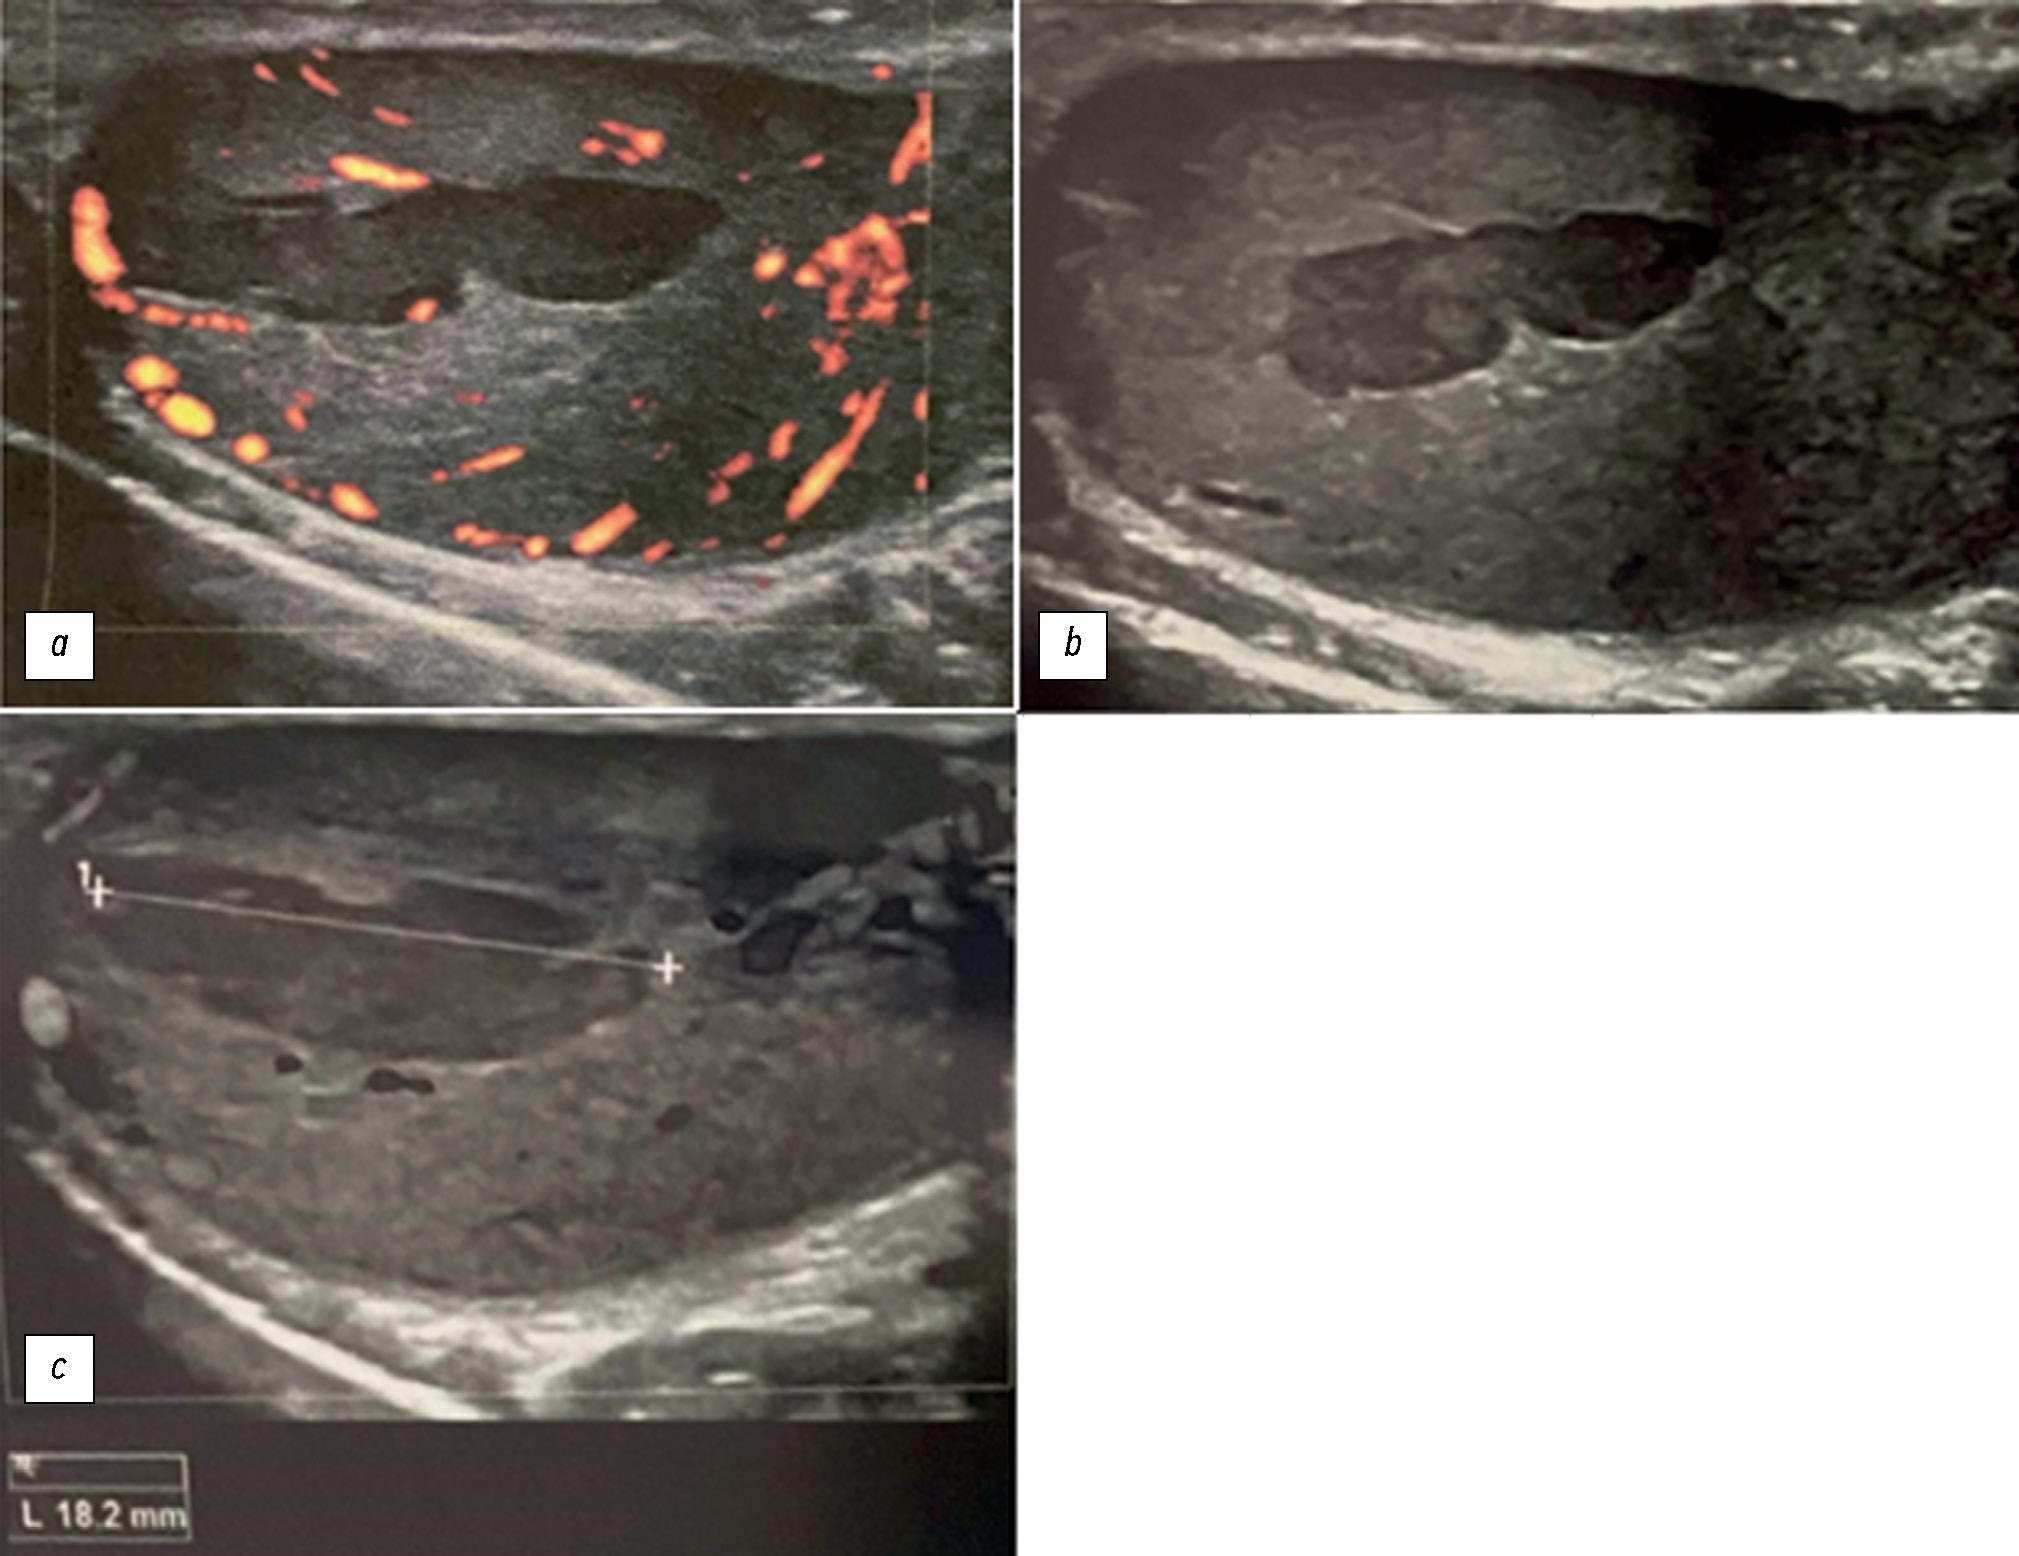

在极少数情况下,急性附睾炎会伴有睾丸缺血和梗塞。 通过临床症状和影像学检查结果很难区分附睾炎和睾丸扭转。在本文中,我们努力扩大用于快速准确鉴别诊断的放射治疗诊断方法的数字图像库。本病例强调了全面放射检查的重要性,以及采用跨学科方法做出准确诊断的必要性。一名24岁的男子因两周前出现左侧睾丸剧烈疼痛而来到医院就诊。据患者称,已经有一段时间出现射精疼痛、性交疼痛、阴囊发红/肿胀、生殖器发炎、恶寒、腹股沟淋巴结肿大、排尿困难和阴囊疼痛。在泌尿科医生的建议下,接受了超声检查和核磁共振成像检查。 影像学检查显示左侧睾丸缺血。根据病史,怀疑患有慢性睾丸附睾炎。由于缺血范围有限,患者无需进行左侧睾丸切除术。 接受了药物治疗。此外,患者还被诊断为左侧精索静脉曲张。对不同磁共振成像序列获得的图像进行了仔细研究。本文描述了一例罕见的睾丸附睾炎病例,这是附睾炎的一种潜在危险并发症。为避免严重后果,当阴囊突然剧烈疼痛时,应考虑到这种并发症的可能性。此案例的描述,能够优化患者的管理方法,并避免不必要的干预。